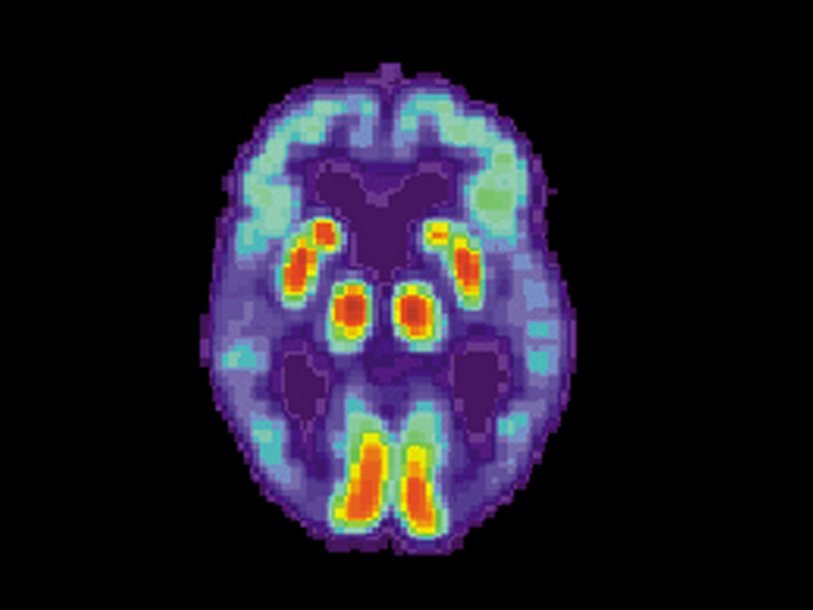

Оказалось, что у пациентов с болезнью кишечника деменция обнаруживалась в 5,5 % случаев, тогда как у контрольных пациентов — в 1,4 %. При этом для лиц с болезнями кишечника средний возраст проявления симптомов деменции составил немногим более 76 лет, что примерно на семь лет раньше по сравнению с контрольной группой. После учета таких факторов, как возраст, пол и другие заболевания, у всех людей с воспалительными заболеваниями кишечника риск развития деменции оказался в 2,5 раза выше, чем у людей без этих болезней. Для болезни Альцгеймера риск повышается в шесть раз. Риск не зависит от конкретного заболевания кишечника.